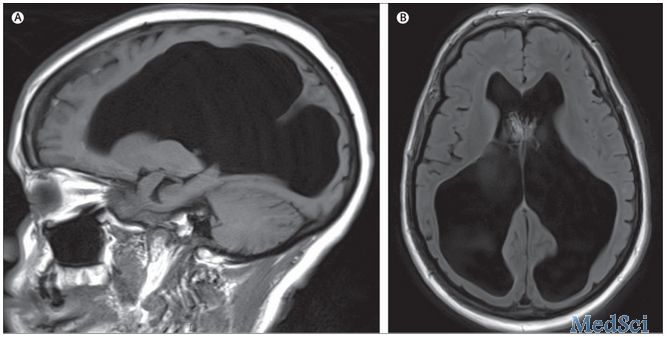

入院后,格拉斯哥昏迷评分(GCS)3,体温39.4°C,心动过速,收缩压170–200 mmHg。双下肢无力,但病理征阴性。考虑较低的GCS评分,行气管插管,但随后出现了低血压,高热,心动过速以及对输液无反应,予以使用血管升压药物。头颅CT和MRI显示大量脑积水。(如图)

脑MRI无强化,T1和T2显示大脑幕上和幕下脑室增宽,无中脑导水管异常

定义:代偿性脑积水(Compensated hydrocephalus),也称为“hydrocephalus ex vacuo”,脑脊液空间代偿性扩大,特征性影像学改变是脑体积减小导致的脑室或蛛网膜下腔扩大。

这个病例充分显示了大脑保持正常意识状态和功能的强大调节能力,尽管有如此严重的慢性脑积水。与正常压力的脑积水相比,代偿性脑积水可以是无症状的,直到出现外部诱因,如这个病例的感染,可导致晕厥甚至突发死亡。临床医生需注意这种情况可能是在无症状患者偶然的体检中发现的。在这个病例中,除非有特殊的临床检查的需求,是不需要进行额外检查的。